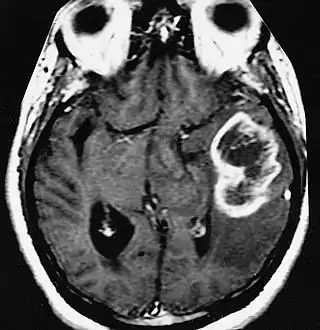

En las imágenes de TC y RM se muestra como una lesión heterogénea, de contorno irregular, que capta contraste en anillo y con un área central necrótica.

La TC muestra una lesión de morfología irregular, predominantemente hipodensa y fuertemente dishomogénea, debido a la presencia de grandes áreas necróticas de más clara hipodensidad y de áreas sólidas hiperdensas. Estas últimas son la expresión de un rápido crecimiento y por lo tanto de una elevada malignidad. Son frecuentes las zonas hemorrágicas, que van desde pequeños focos a grandes áreas hemáticas que pueden cubrir toda la lesión. Es característica la morfología en "mariposa" si el tumor se asienta en ambos hemisferios a través del cuerpo calloso.

Tras la aplicación de contraste aparecen gruesos anillos alrededor de las áreas necróticas. En la RM, la parte sólida aparece hipointensa en T1 e hiperintensa en T2 con zonas de señal más elevada en las partes de mayor celularidad. Las áreas necróticas, hiperintensas en T2, pueden presentarse hipo-, iso- o hiperintensas en T1 en función del contenido proteico o de productos de la degradación de la hemoglobina. El realce tras el contraste suele ser intenso e irregular en la periferia del tumor e identifica sobre todo la componente celular "proliferativa" de la neoplasia. Son comunes las áreas puntiformes y serpiginosas de ausencia de señal de flujo, asociadas a la presencia de una neovascularización rica. Estos vasos de neoformación patológica carecen de barrera hematoencefálica, lo que explica tanto la abundante impregnación como el edema vasogénico perilesional (véase la sección anterior), debido al paso de líquido al medio extracelular.[71][72]